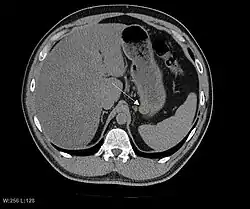

CT image of a GIST in the gastric cardia. The lesion appears submucosal, is hypervascular and protrudes intraluminally. Upper GI bleeding led to endoscopy, finding an ulcerated mass.

The purpose of radiologic imaging is to locate the lesion, evaluate for signs of invasion and detect metastasis. Features of GIST vary depending on tumor size and organ of origin. The diameter can range from a few millimeters to more than 30 cm. Larger tumors usually cause symptoms in contrast to those found incidentally which tend to be smaller and have better prognosis.[4][20] Large tumors tend to exhibit malignant behavior but small GISTs may also demonstrate clinically aggressive behavior.[21]

Preferred imaging modalities in the evaluation of GISTs are CT and MRI,[23]: 20–21  and, in selected situations, endoscopic ultrasound. CT advantages include its ability to demonstrate evidence of nearby organ invasion, ascites, and metastases. The ability of an MRI to produce images in multiple planes is helpful in determining the bowel as the organ of origin (which is difficult when the tumor is very large), facilitating diagnosis.